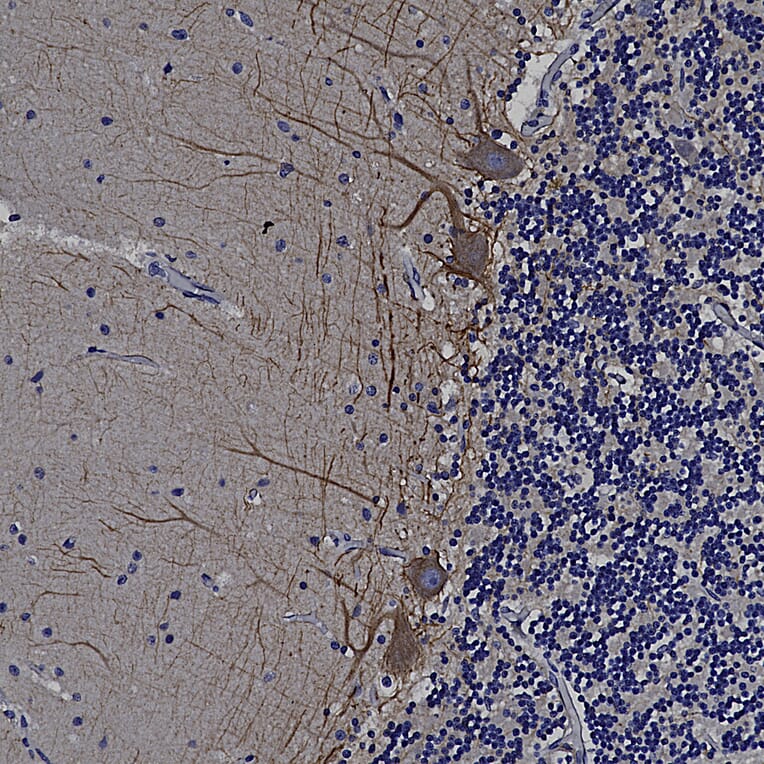

Immunohistochemistry analysis of a formalin fixed paraffin embedded human cerebellum section with Anti-alpha Internexin Antibody (A85441), detected with DAB (brown) using the Vector Labs ImmPRESS method and reagents with citra buffer retrieval. Counterstained with Hematoxylin (blue). The Anti-alpha Internexin Antibody (A85441) labels axons and dendrites of neuronal cells, outlining the Purkinje cells and parallel fibers in this image. Note: this antibody performs well in testing with both 4% PFA and standard NBF fixed rat, mouse, and human tissues.